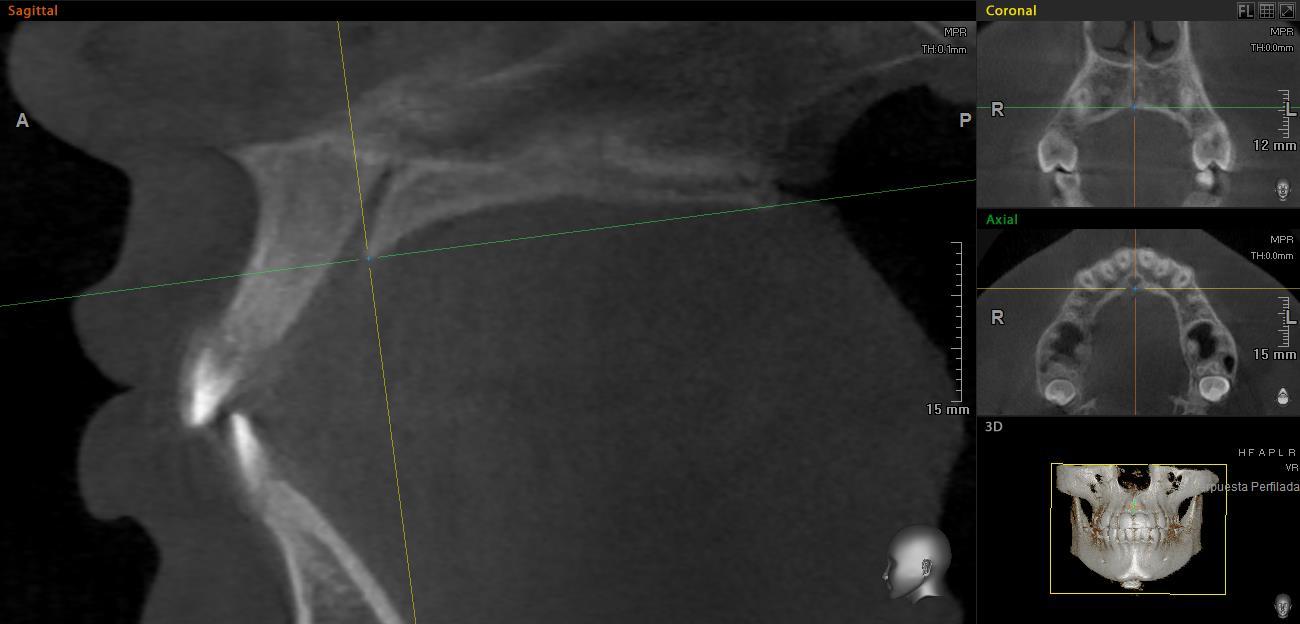

Las imágenes fueron orientadas utilizando el mismo protocolo. En el corte sagital, la intersección entre el plano sagital y coronal se coloca sobre el borde posterior del foramen incisivo, de manera que el plano axial coincida con la espina nasal posterior (Figura 1).

Plano axial posicionado en el borde posterior del foramen incisivo y espina nasal posterior